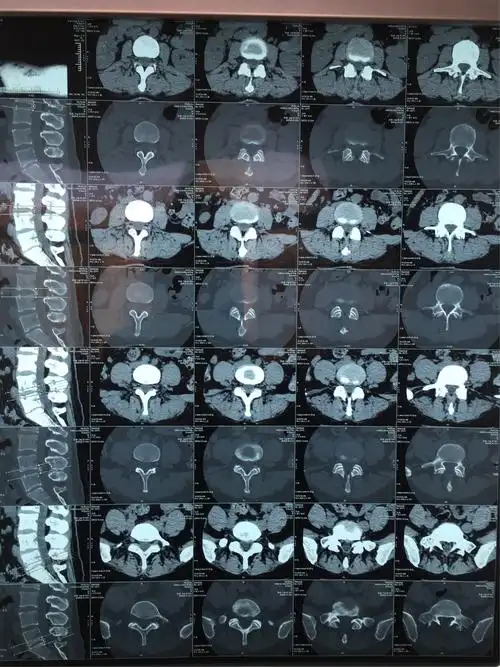

病人术前片子,腰五骶一椎间盘突出.

腰间盘突出ct图,请帮忙看下如何治疗好

椎间孔镜技术治疗腰椎间盘突出症一例

腰椎间盘突出的影像诊断

腰椎ct显示l4-5椎间盘突出,腰椎管狭窄

腰椎间盘突出症的影像学检查